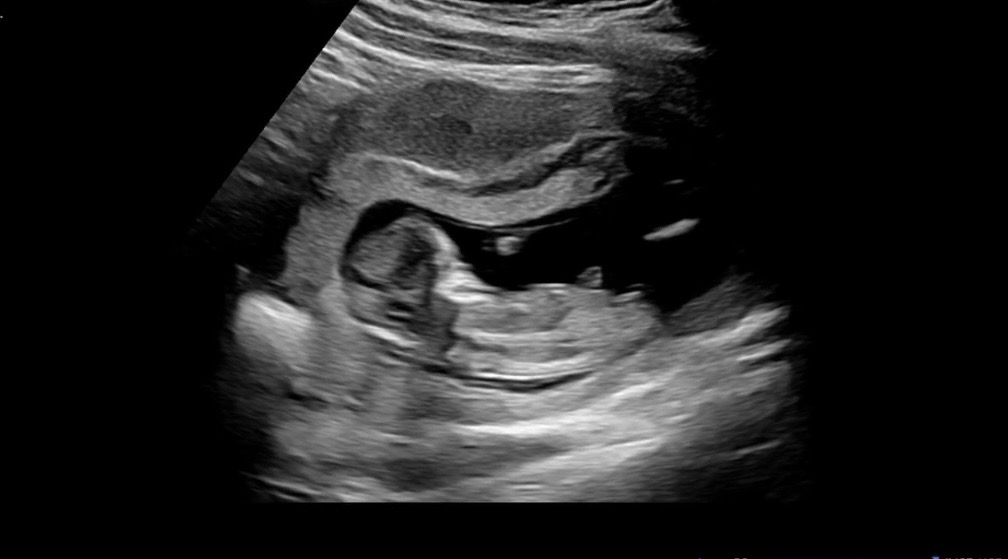

12주 각도법 투표 부탁드려욤💙🩷

과연..!!!!